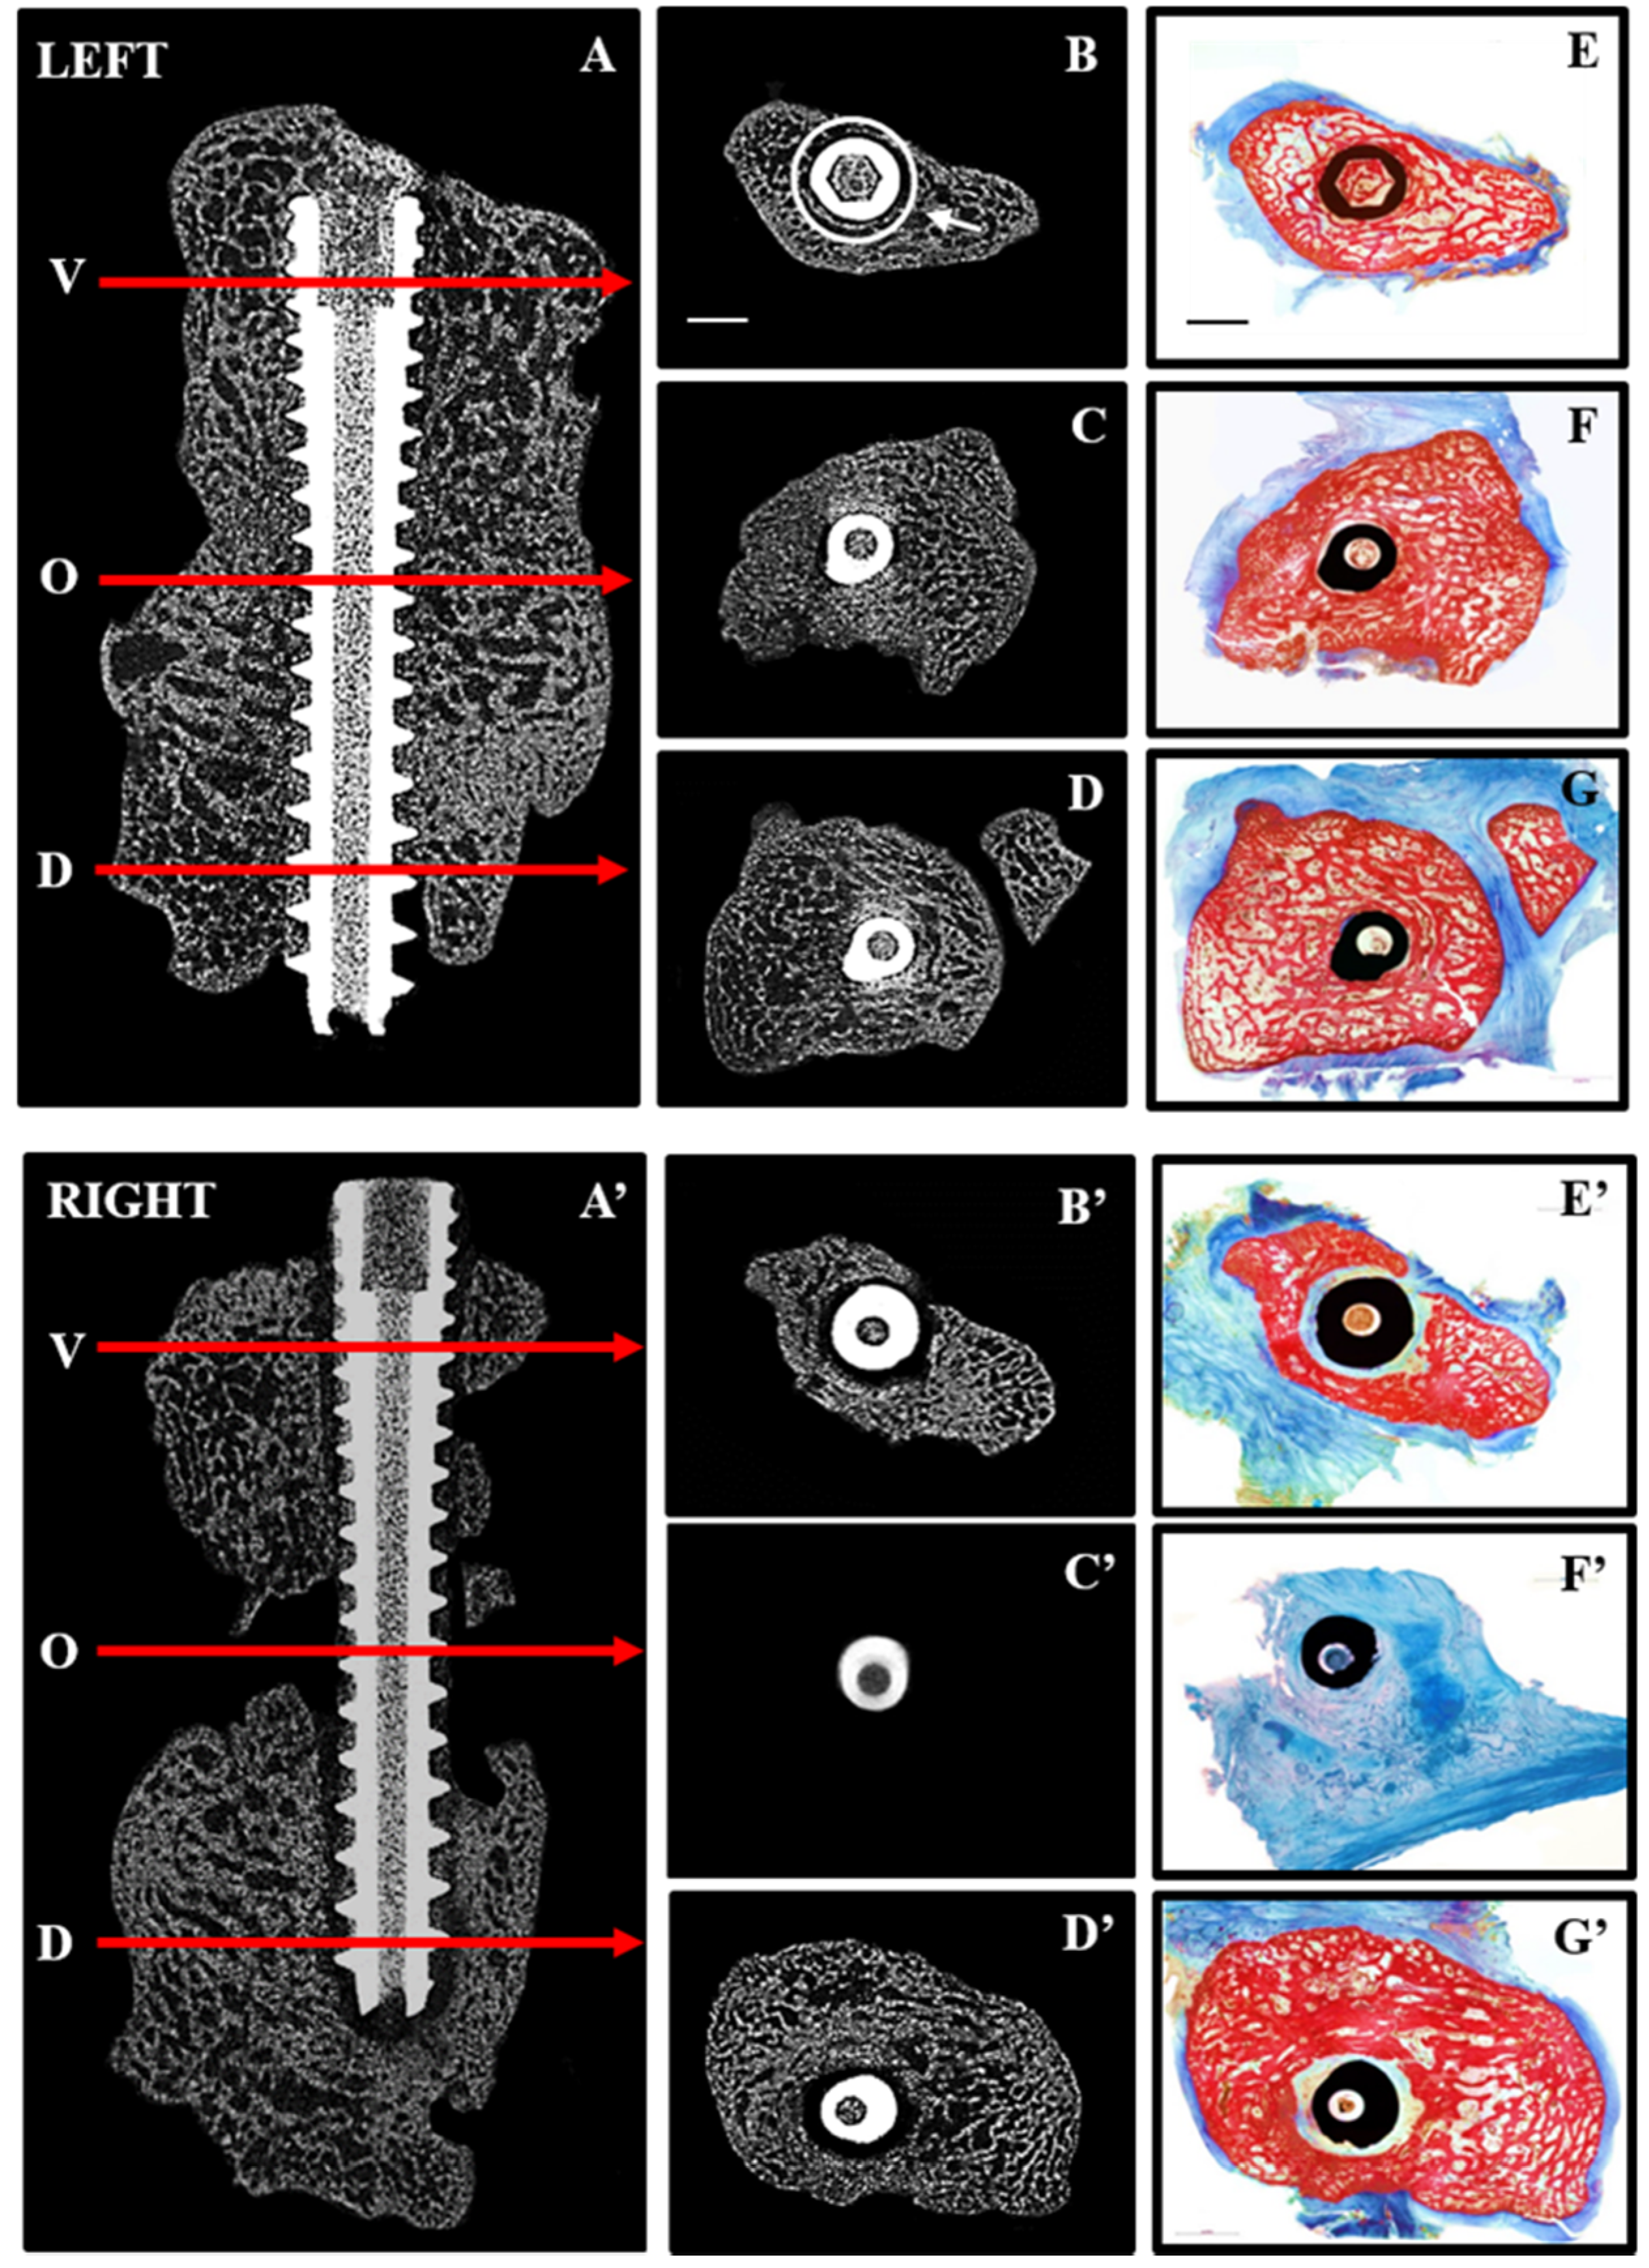

Figure 3.

Repair after immediate (LEFT) and delayed (RIGHT) fixation: 2D micro CT images are shown in the sagittal plane (A,A’) indicating the position along the screw (arrows) at which transaxial 2D images are shown for the volar (V,B,B’), osteotomy site (O,C,C’) and dorsal (D,D,D’) aspects of the radiocarpal bones. Corresponding histological sections from the same levels (E–G,E’–G’) were stained with Alizarin red and Methylene blue to distinguish mineralized (red) from soft (blue) tissue. Complete bridging occurred with immediate fixation (A,C) whereas little bone was seen in the osteotomy site (A’,C’) with delayed fixation. Histological sections confirmed the presence of bone in the osteotomy site with immediate fixation (F) and its absence with delayed fixation (F’). Arrow (B) points to ROI used for quantitative micro CT analyses and scale bars (B,E) represents 2 mm.

In contrast to immediate fixation (IF) (Figure 3A–G), where bone was seen adjacent to the screw along its entire length, delayed fixation (DF) resulted in soft tissue along the length of the screw (Figure 3A’–G’). This is most noticeable on the histological sections where bone is red and soft tissue blue. Quantitative micro CT (Figure 4) revealed significantly less bone (BV/TV) adjacent to the screw at the osteotomy site (white circle in Figure 3B) with DF compared with IF.